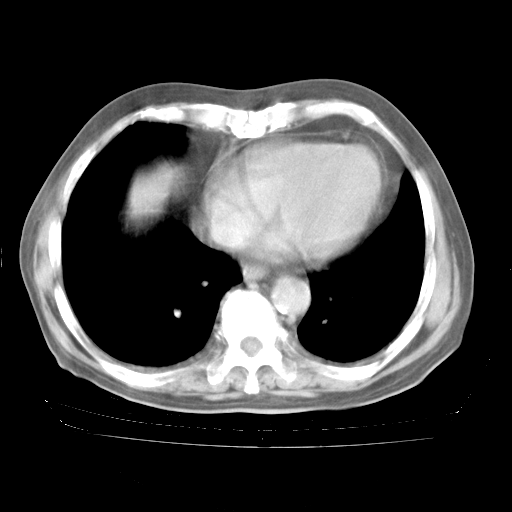

4月28日肺部CT——再次出现类似去年5月9日——透光度降低,“间质性”改变。

4月28日肺部CT——再次出现类似去年5月9日——磨玻璃样、间有“粟粒样”改变。

个人阅读4.14日肺部CT平扫:纵隔窗无异常,但肺窗示:双下肺内、后基底段有片絮状侵润影,部位以后基底段为著,以间质改变为主,呈急性肺泡炎征像,和首次住院影像学有相似之处。仅是个人读片,明日请相关专家再读片哈。其它建议同上。

1、108#的是4月14日的胸部CT(发此贴时还没看着28日的CT)。14日的胸部CT其实已经出现改变(如108#所述),个人认为28日的胸部CT除纵膈窗疑似有双侧胸膜增厚或少量胸积液(可行胸部B超明确)外,与4月14日对照病变有所加重;2、已经给予“异烟肼、利福平、乙胺丁醇”抗痨治疗?如果是,甲强龙80mg可缓慢减量;如果环磷酰胺已停用,暂不使用;3、中性粒细胞92%,明显升高,目前体温情况?注意合并细菌感染可能,使用左氧氟沙星情况下,是否联用B-内酰胺类抗菌药物?另外是查免疫全套非风湿全套。